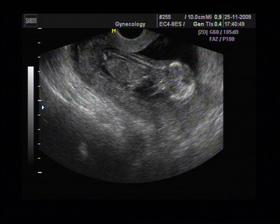

8/10 jsme se byli podívat u paní doktorky, zda testy nelhaly - a ono n e. Puclík měřil 0,37cm a co je důležité - srdíčko už funguje. Táta s Pepínem byli v ordinaci s námi, a když se na monitoru objevilo mimi, tak ho Pepíno pozdravil - udělal mu "ahoj" 🙂 oba nás to s Honzou dojalo. Další kontrola 22/10.